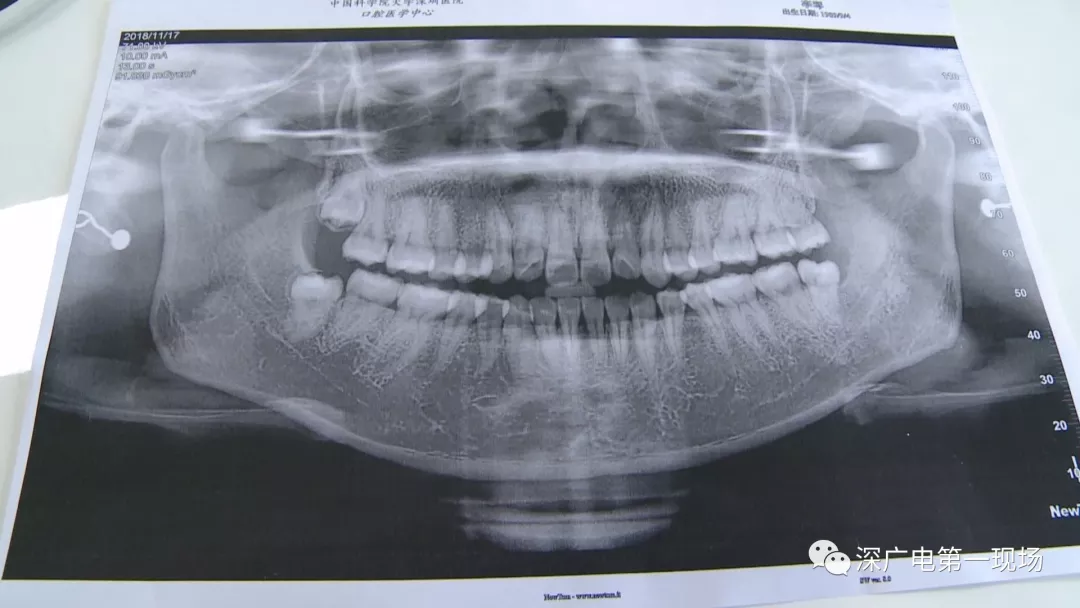

拔一顆智齒一千六?! 深圳這位女士默默的放下了賬單……

隨后,李女士在網(wǎng)上查詢,發(fā)現(xiàn)拔智齒的收費(fèi)都是參差不齊,也沒有參考標(biāo)準(zhǔn)。在李女士提供的拔牙收費(fèi)單上,記者注意到,除了一些拔牙必用的藥物外,還有一些輔助工具的費(fèi)用。

中國科學(xué)院大學(xué)深圳醫(yī)院口腔科主任賈岳介紹,對于不同患者的牙齒,它的治療方法都不一樣,所以不同牙齒,醫(yī)院收費(fèi)的標(biāo)準(zhǔn)也各不相同。牙齒的治療方案,都是根據(jù)患者牙齒具體情況來制定,然后再去收費(fèi),同時(shí)也會(huì)參考病人實(shí)際情況來做不同的治療項(xiàng)目。